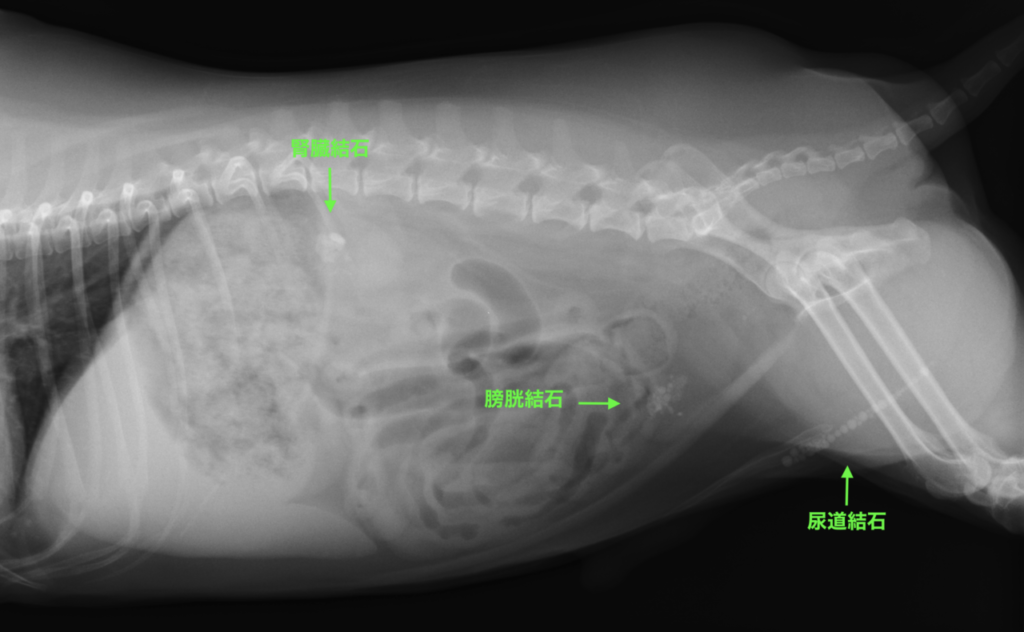

犬 膀胱結石. 犬の尿石症 コーギーの1例 手術で膀胱結石を摘出しました 尿石症とは? 尿石症(尿路結石)とは、尿路である腎臓(腎盂)、尿管、膀胱または尿道のいずれかに結石が形成される病気です。 猫の特発性膀胱炎(FIC) 猫のおしっこに関する病気を総称して猫下部尿路疾患(FLUTD)と呼びます。 その症状として、血尿、頻尿、排尿時に痛がる、ト 排尿障害 〝何度. 膀胱と腎臓を繋ぐ管に出来る尿管結石 3膀胱に出来る膀胱結石 4尿道に石が詰まる尿道結石 犬の結石には4種類あり原因となる野菜・食べ物は異なる. 犬の膀胱・尿道結石の一例 小手指ペットクリニック 16年11月28日 8才のワンちゃんが、昨日から尿が出ずに元気がないとのことで来院されました。 レントゲンを撮ると、膀胱内に7個程度、尿道に3個(ペニス先端から10cmに2個、13cmに1個)の石が.

犬 膀胱結石・尿道結石 チワワ 10歳11ヶ月齢 去勢オス 71kg 頻尿と血尿、排尿障害を主訴に来院 腹部と陰茎の触診検査にて結石症が疑われたため、 レントゲン検査を行い、膀胱結石および尿道結石、腎臓結石と診断した 尿道内にぎっしりとつまった結石は、カテーテルにて膀胱内に押し戻し、膀胱切開にて膀胱結石を摘出した 腎臓結石はに対する外科処置は、腎臓. 犬の膀胱結石 更新日時: ミニチュアダックスフンド、オス (去勢)、11歳 《主訴》血尿、排尿しづらい (少量ずつしか出ない) 《検査》①腹部レントゲン検査 膀胱に結石と思われる不透過性陰影を多数確認 ②腹部超音波検査 膀胱内に結石と思われるシャドーを引く高エコー物を多数確認 ③尿.